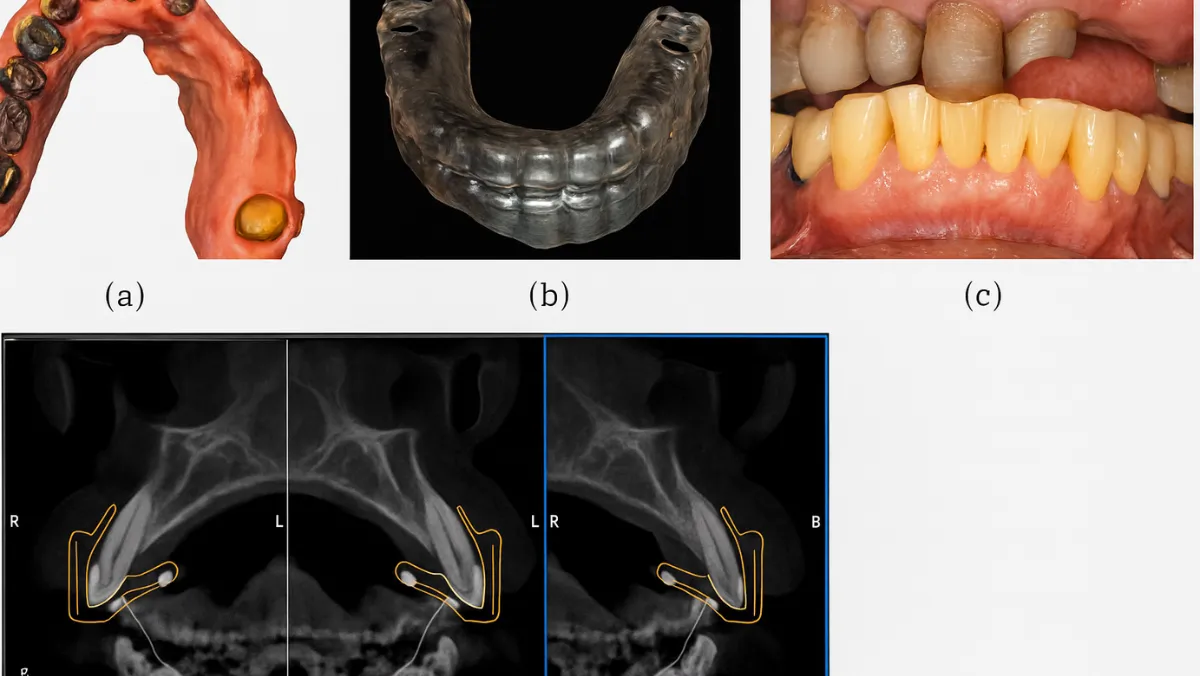

We utilize CBCT-guided treatment planning in dental implant placement, and full mouth rehabilitation. This approach ensures the consistent delivery of superior patient outcomes in both function and esthetics.

• Dental Implant Planning: CBCT guided planning is indispensable in the placement of dental implants. By using 3D imaging, dental professionals can analyze bone volume and density, identify potential risks, and create an optimal placement strategy for dental implants. This ensures that implants are placed precisely in the ideal location, improving the success rate and longevity of the implants.